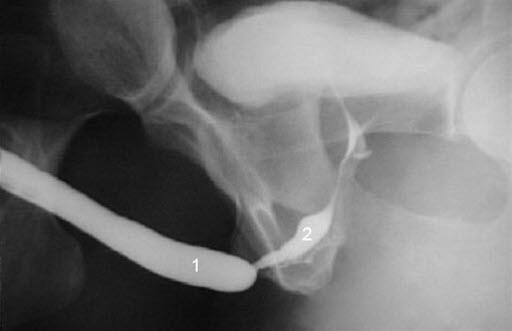

Innsnevring i urinrøret (1 - ytre del)Innsnevring av urinrøret betegnes på fagspråket uretrastriktur (uretra = urinrør, striktur = trangt parti). Urinrøret går fra blæren og ut. En innsnevring av urinrøret kan være lokalisert i ytre del av urinrøret eller i indre del av urinrøret (inn mot blæren). De fleste innsnevringer befinner seg i ytre del av urinrøret som innbefatter urinrørets passasje gjennom penis og penisroten (bulbus). En ubehandlet innsnevring i urinrøret kan disponere for urinveisinfeksjoner, føre til akutt stopp i vannlatingen (akutt urinretensjon), resultere i fortykket urinblærevegg og irritasjon fordi urinblæren over lang tid må presse ut urinen mot motstand, og på sikt prostatitt. Lengden og graden av innsnevring avgjør risikoen for komplikasjoner.